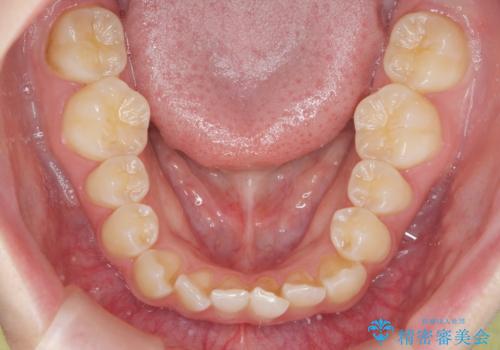

前歯のねじれを治したい マウスピース矯正治療

- 前歯のねじれを改善し、きれいな歯並びにしたい!と矯正治療を希望され来院されました。

マウスピース矯正システム、インビザラインのシミュレーションを用いて最終的な歯の位置をしっかりと確認したのち、きれいな歯並びとなるようマウスピース矯正治療を開始します。

ねじれとともに突き出たように見えていた前歯も見た目が大きく改善し、喜んでいただくことができました。